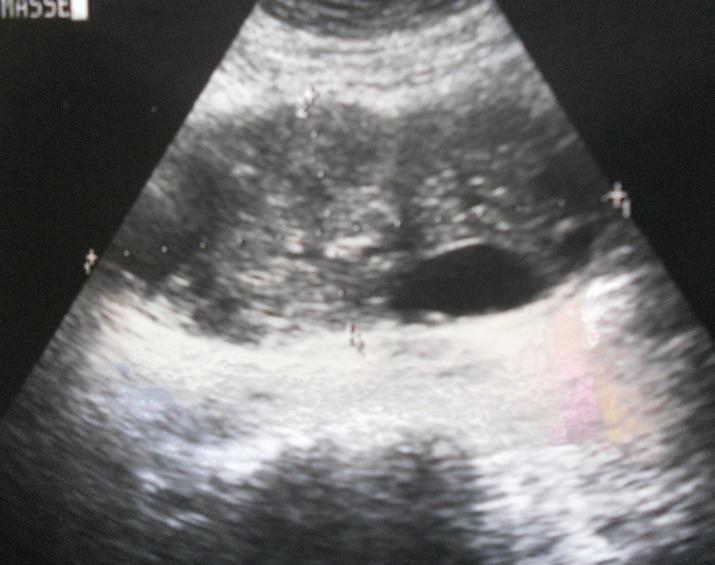

Hydatid disease is an endemic problem in some areas of the world. Common sites include liver and lungs. We report an unusual case of isolated primary Hydatid cyst of small gut mesentery. Characteristics of this uncommon location, mechanism, diagnostic difficulties, and treatment are discussed.

包虫病是世界上一些地区的地方病问题。常见部位包括肝脏和肺。我们报告了一例罕见的孤立性小肠系膜原发性包虫囊肿病例。讨论了这种不常见部位的特征、发病机制、诊断困难及治疗方法。